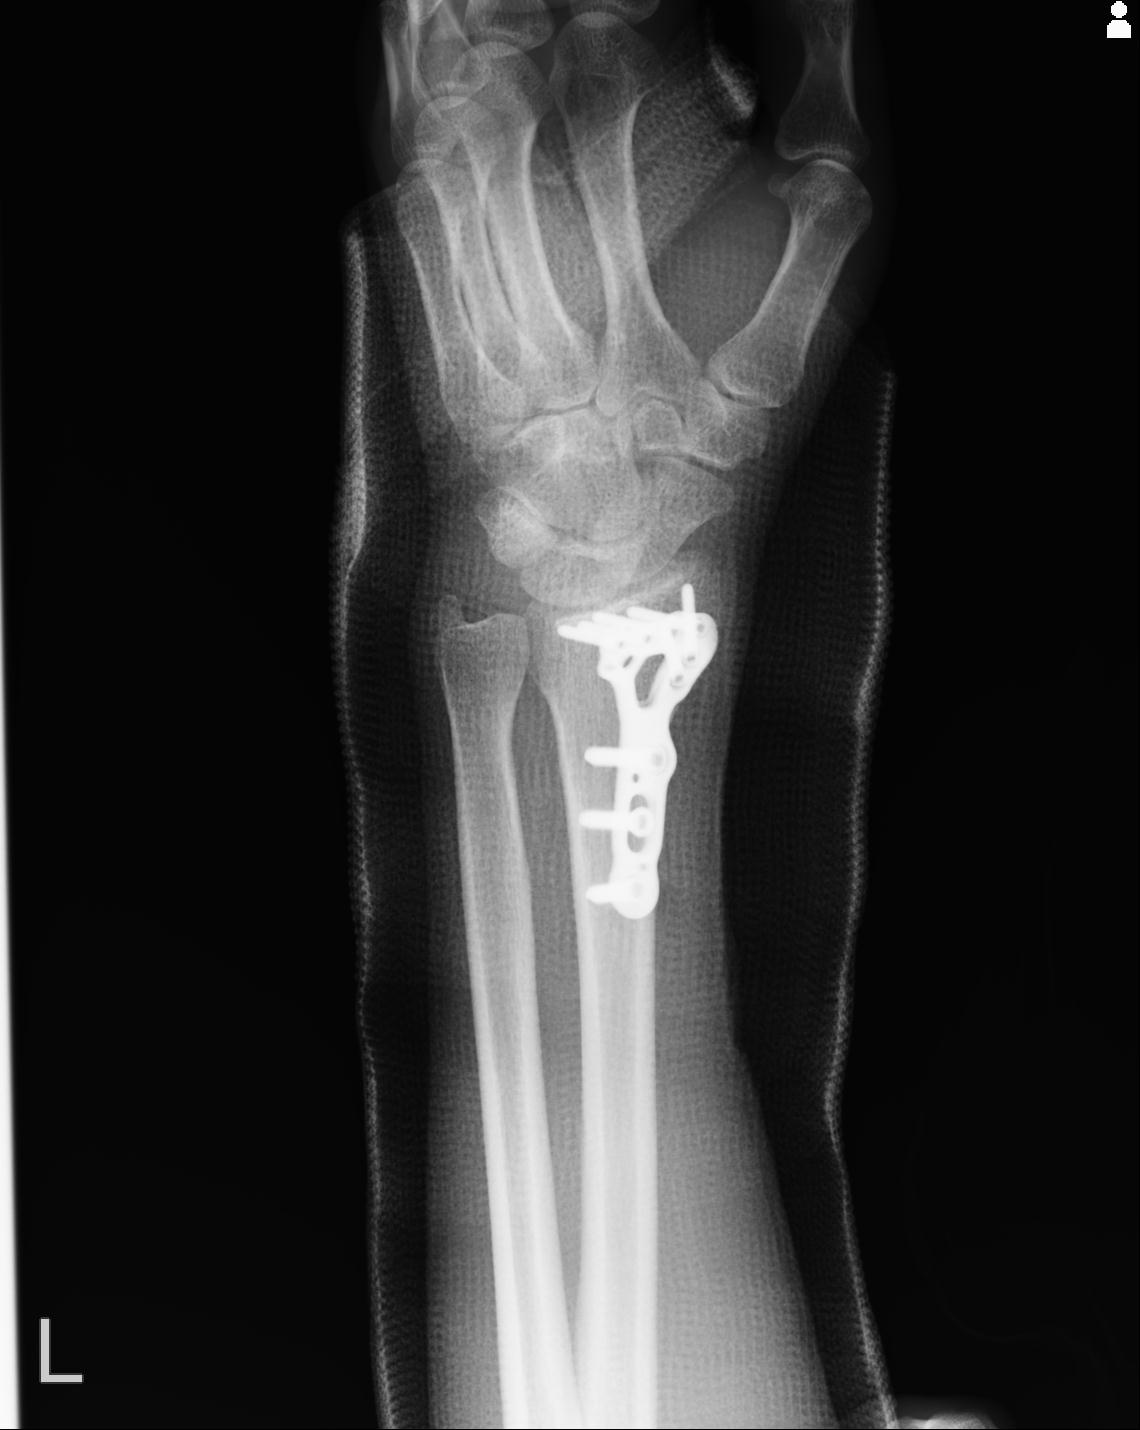

102766 1/5 1/12 左手関節 4R 28歳男性 左橈骨遠位端